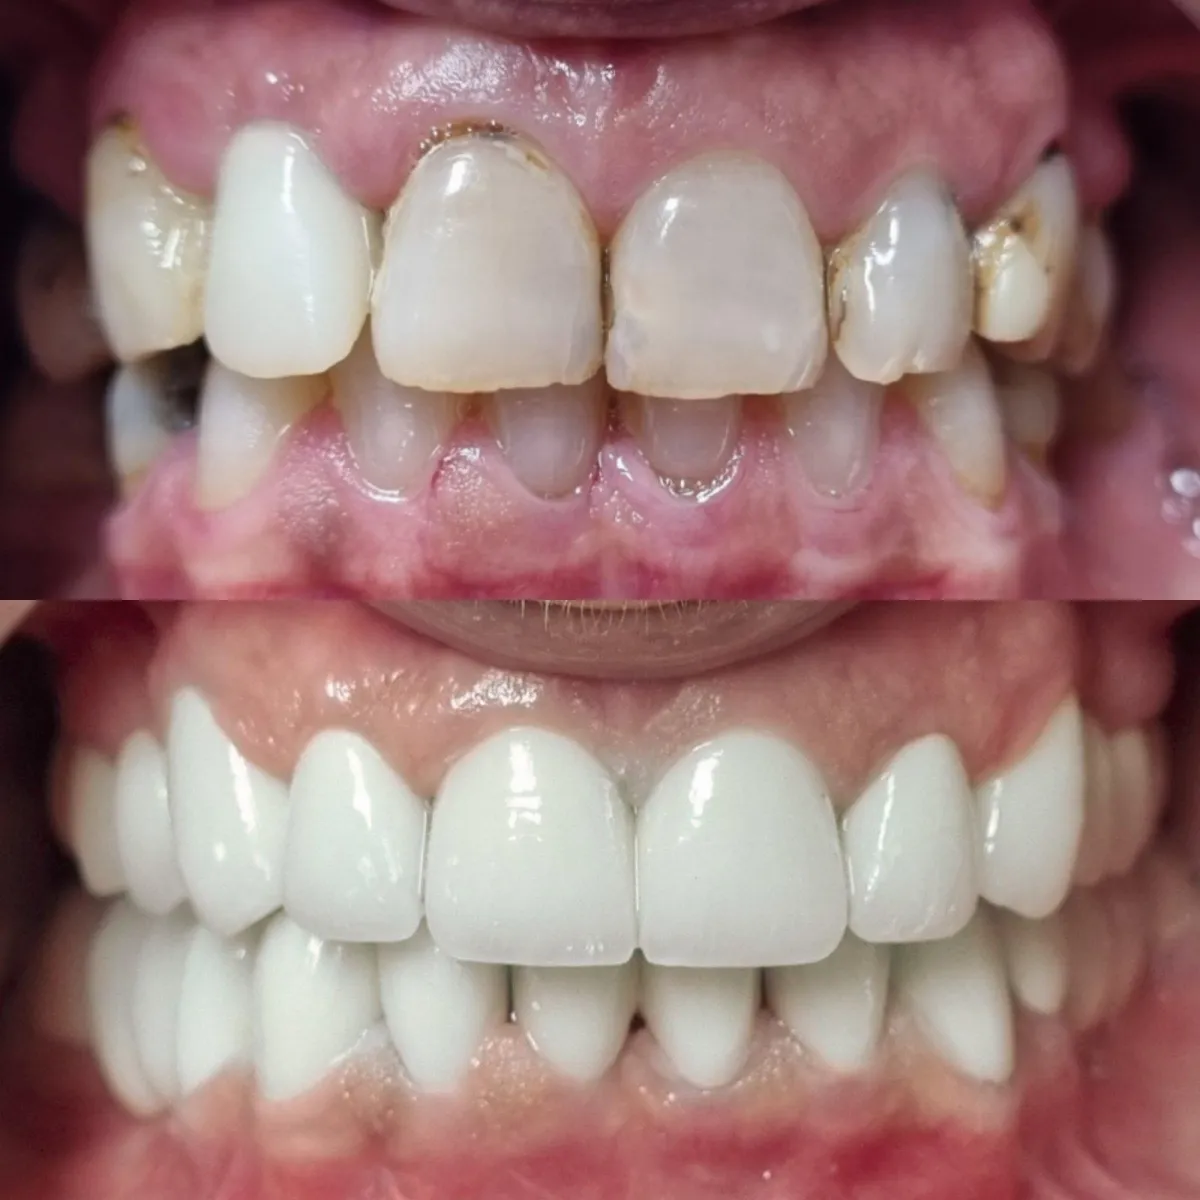

Pogledajte našu galeriju istaknutih radova u Dental Studio dr. Jusić. S ponosom vam predstavljamo rezultate našeg truda, stručnosti i posvećenosti. Bilo da se radi o estetskim zahvatima, implantatima ili ortodontskim tretmanima, naši zadovoljni pacijenti su najbolji dokaz kvalitete naših usluga.